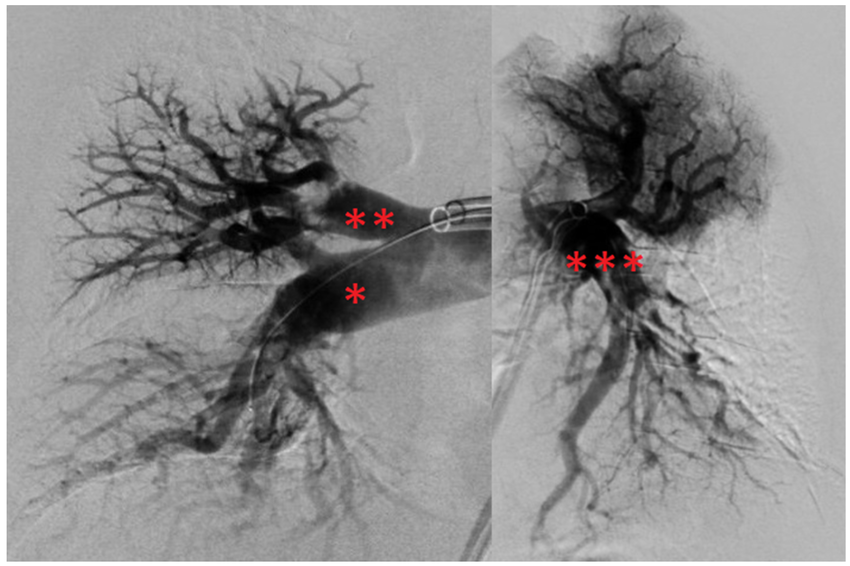

Endovascular DSA (Digital Subtraction Angiography) and Mechanical Thrombectomy are advanced, minimally invasive procedures used for diagnosing and treating stroke and other vascular conditions of the brain.

Digital Subtraction Angiography is a high-resolution imaging technique that provides detailed visualization of blood vessels in the brain and spine. It helps in diagnosing aneurysms, arteriovenous malformations (AVMs), stenosis, and vascular blockages.

Mechanical Thrombectomy is an emergency stroke treatment performed to remove a blood clot from a blocked brain artery. It is most effective when done within 6–24 hours of stroke onset.